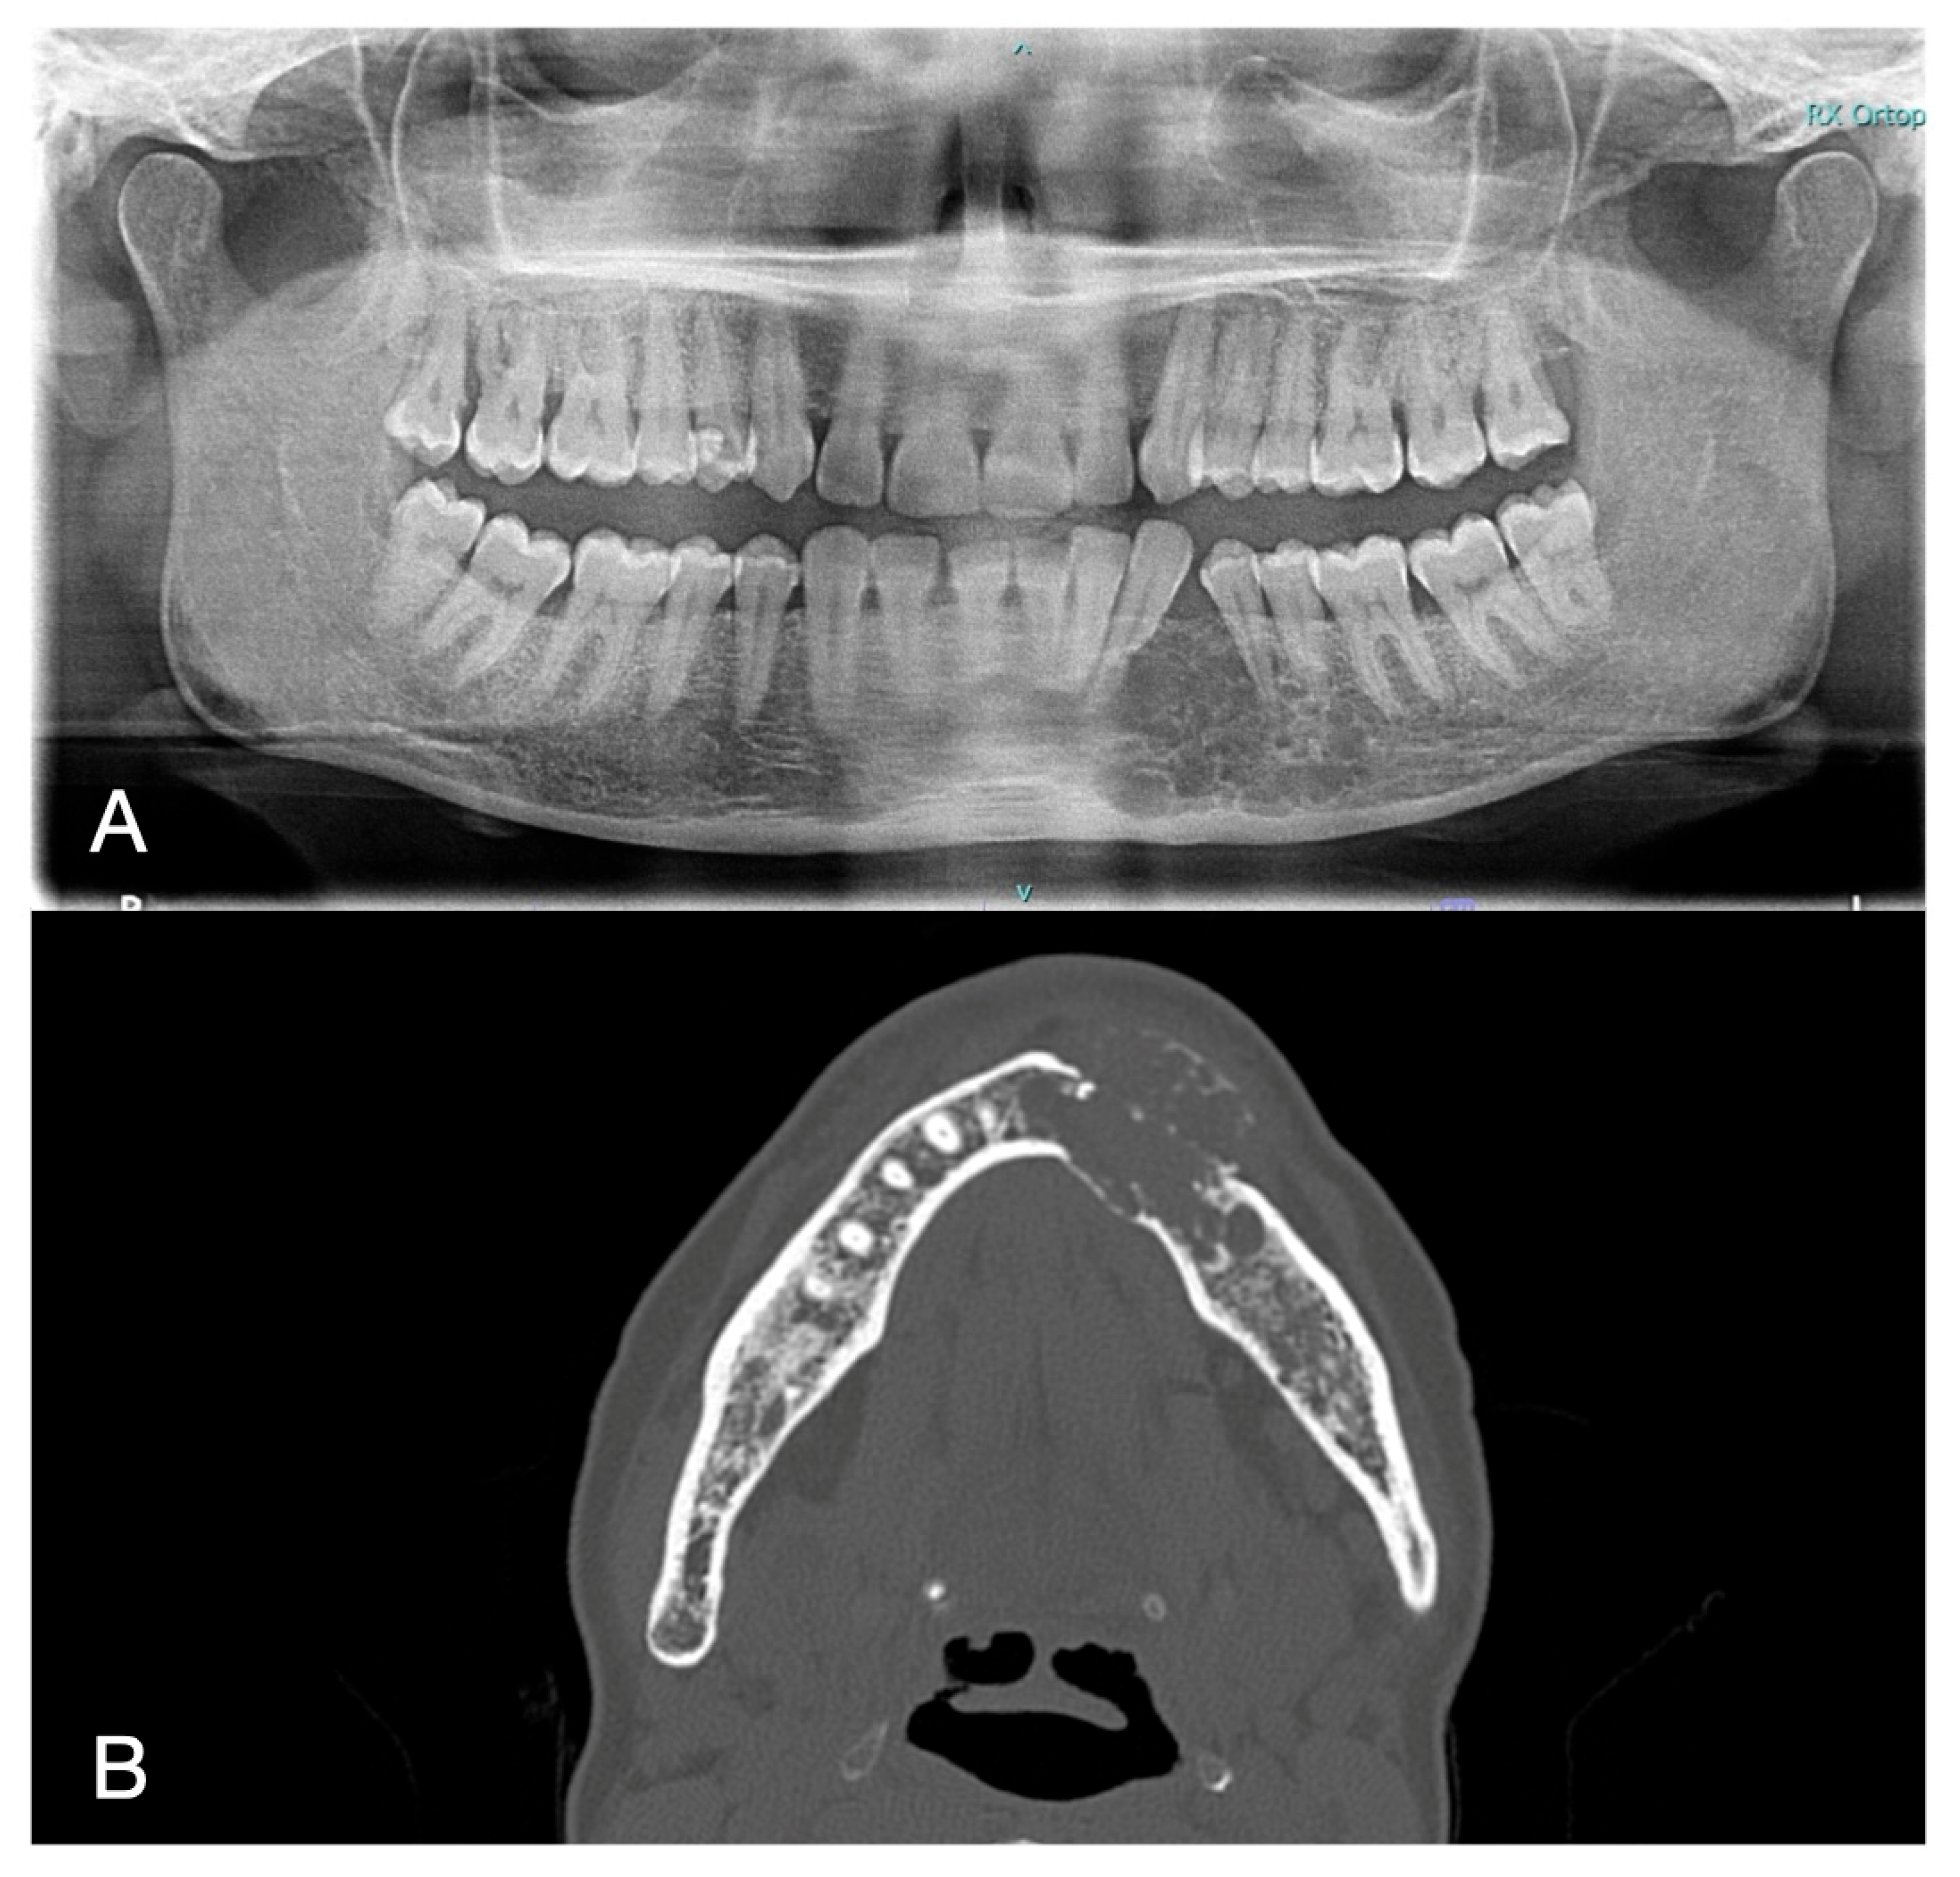

The pulp vitality test (cold test) was positive for the elements 3.2–3.3–3.4–3.5 and 3.6, and no pathological pocket probing depth was detected in any of the involved teeth. The bi-dimensional OPG showed a wide radiolucent lesion, located between the canine and second premolar on the left side of the mandible. The second level tri-dimensional imaging CT scan (axial tomography) showed a radiolucent mass in the left mandibular body, with erosion of the mandibular cortex. The two-dimensional and three-dimensional imaging findings are presented in Figure 2.

Figure 2. OPG (A) and CT (B) radiological findings.